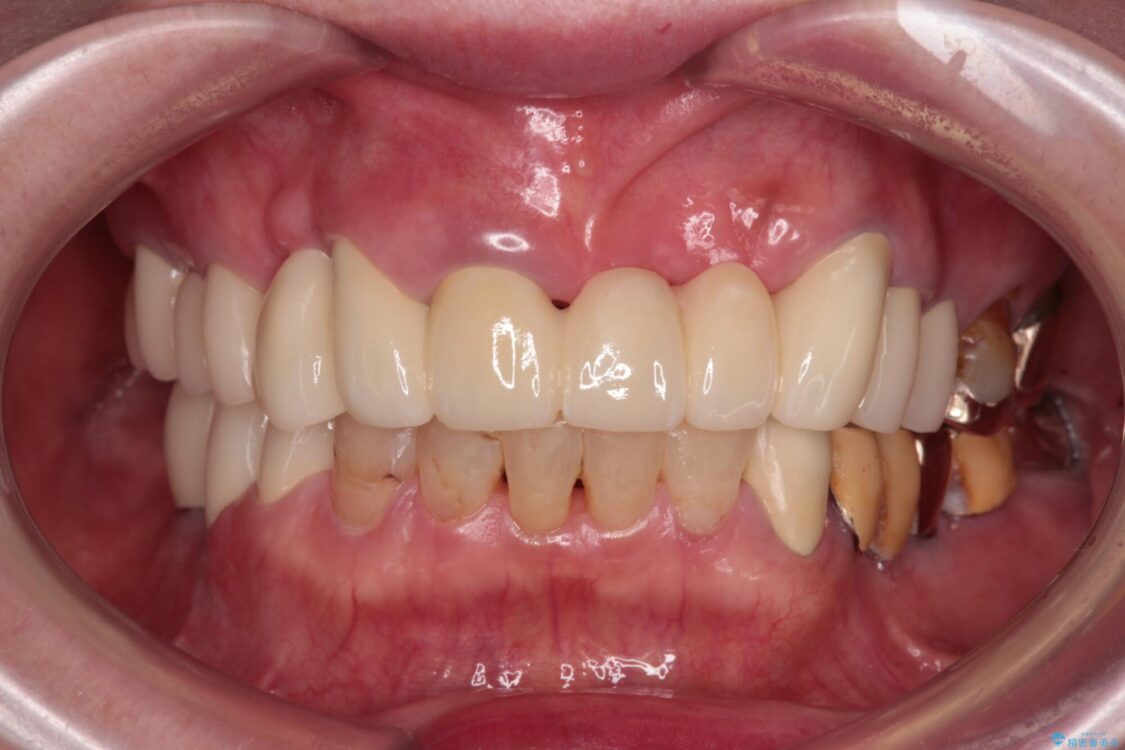

抜歯の必要な前歯や、以前治療した前歯のクラウンの外観を気にして来院された患者様です。

クラウンが不適合であったり、根管治療の必要なほどの痛みのある歯であったり、見た目の気になる前歯などをオールセラミッククラウンに補綴治療を行うこととしました。

治療前